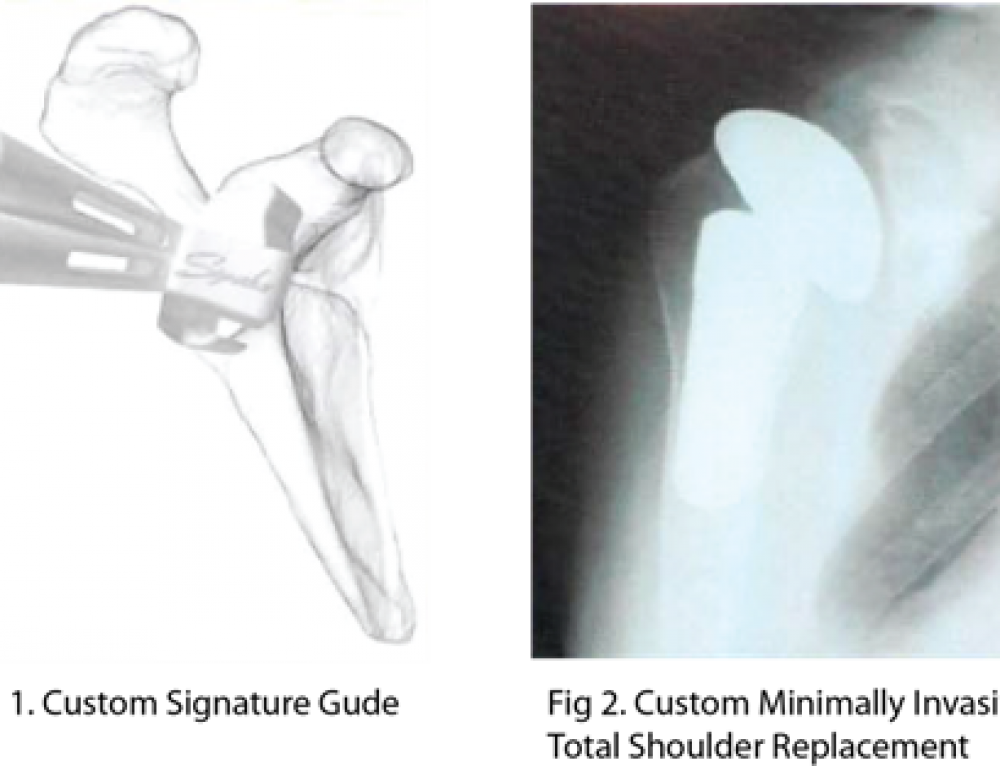

Shoulder Replacement Laud Clinic

Minimally Invasive Shoulder Replacement TESS Shoulder Arthroplasty Shoulder Replacement Manufacturers Stryker’s shoulder id implant is intended to replace the shoulder joint in order to relieve pain and to improve mobility in comparison to. The titan modular total shoulder system was designed to be a preserving option for patients needing total shoulder arthroplasty. Find your reverse shoulder prosthesis easily amongst the 25 products from the leading brands (stryker, medicalex, enovis,.) on. Shoulder Replacement Manufacturers.